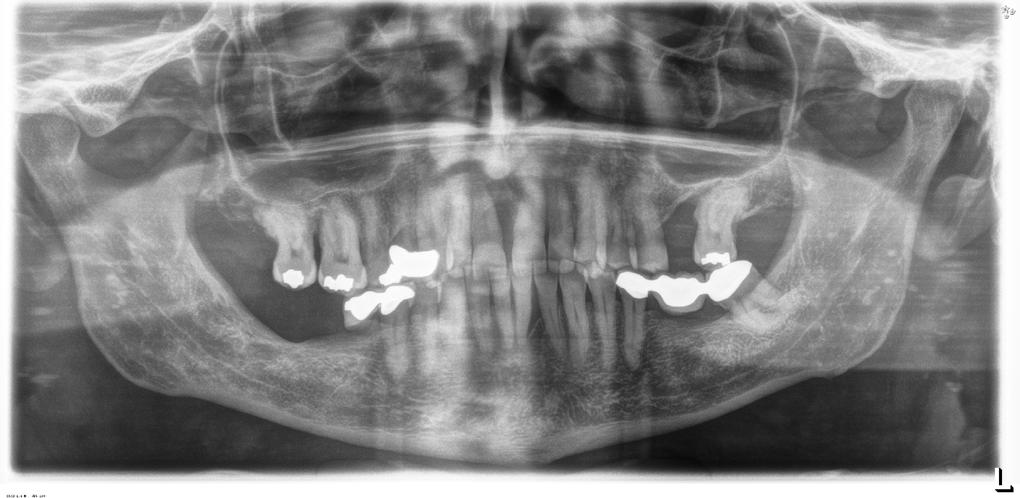

Negli ultimi anni sono presenti in letteratura studi che riportano riabilitazioni implantoprotesiche effettuate in questa tipologia di pazienti , fornendo loro nuove prospettive terapeutiche.